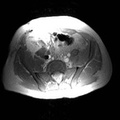

RADIOLOGY: KIDNEY: Case# 33985: PTLD. Renal transplant patient. 1) Echogenic mass with cystic component in the renal transplant hila causing focal stenosis in the main renal artery. The appearance would be most consistent with post-transplant lymphoproliferative disorder. Alternatively, renal abscess in this area cannot be excluded. Correlation with clinical history recommended. 2) Marked hydronephrosis with internal debris within the collecting system of the transplant kidney. This is felt to likely be due to obstruction from the above mass. 3) Small bilateral pleural effusions and small amount of ascites.